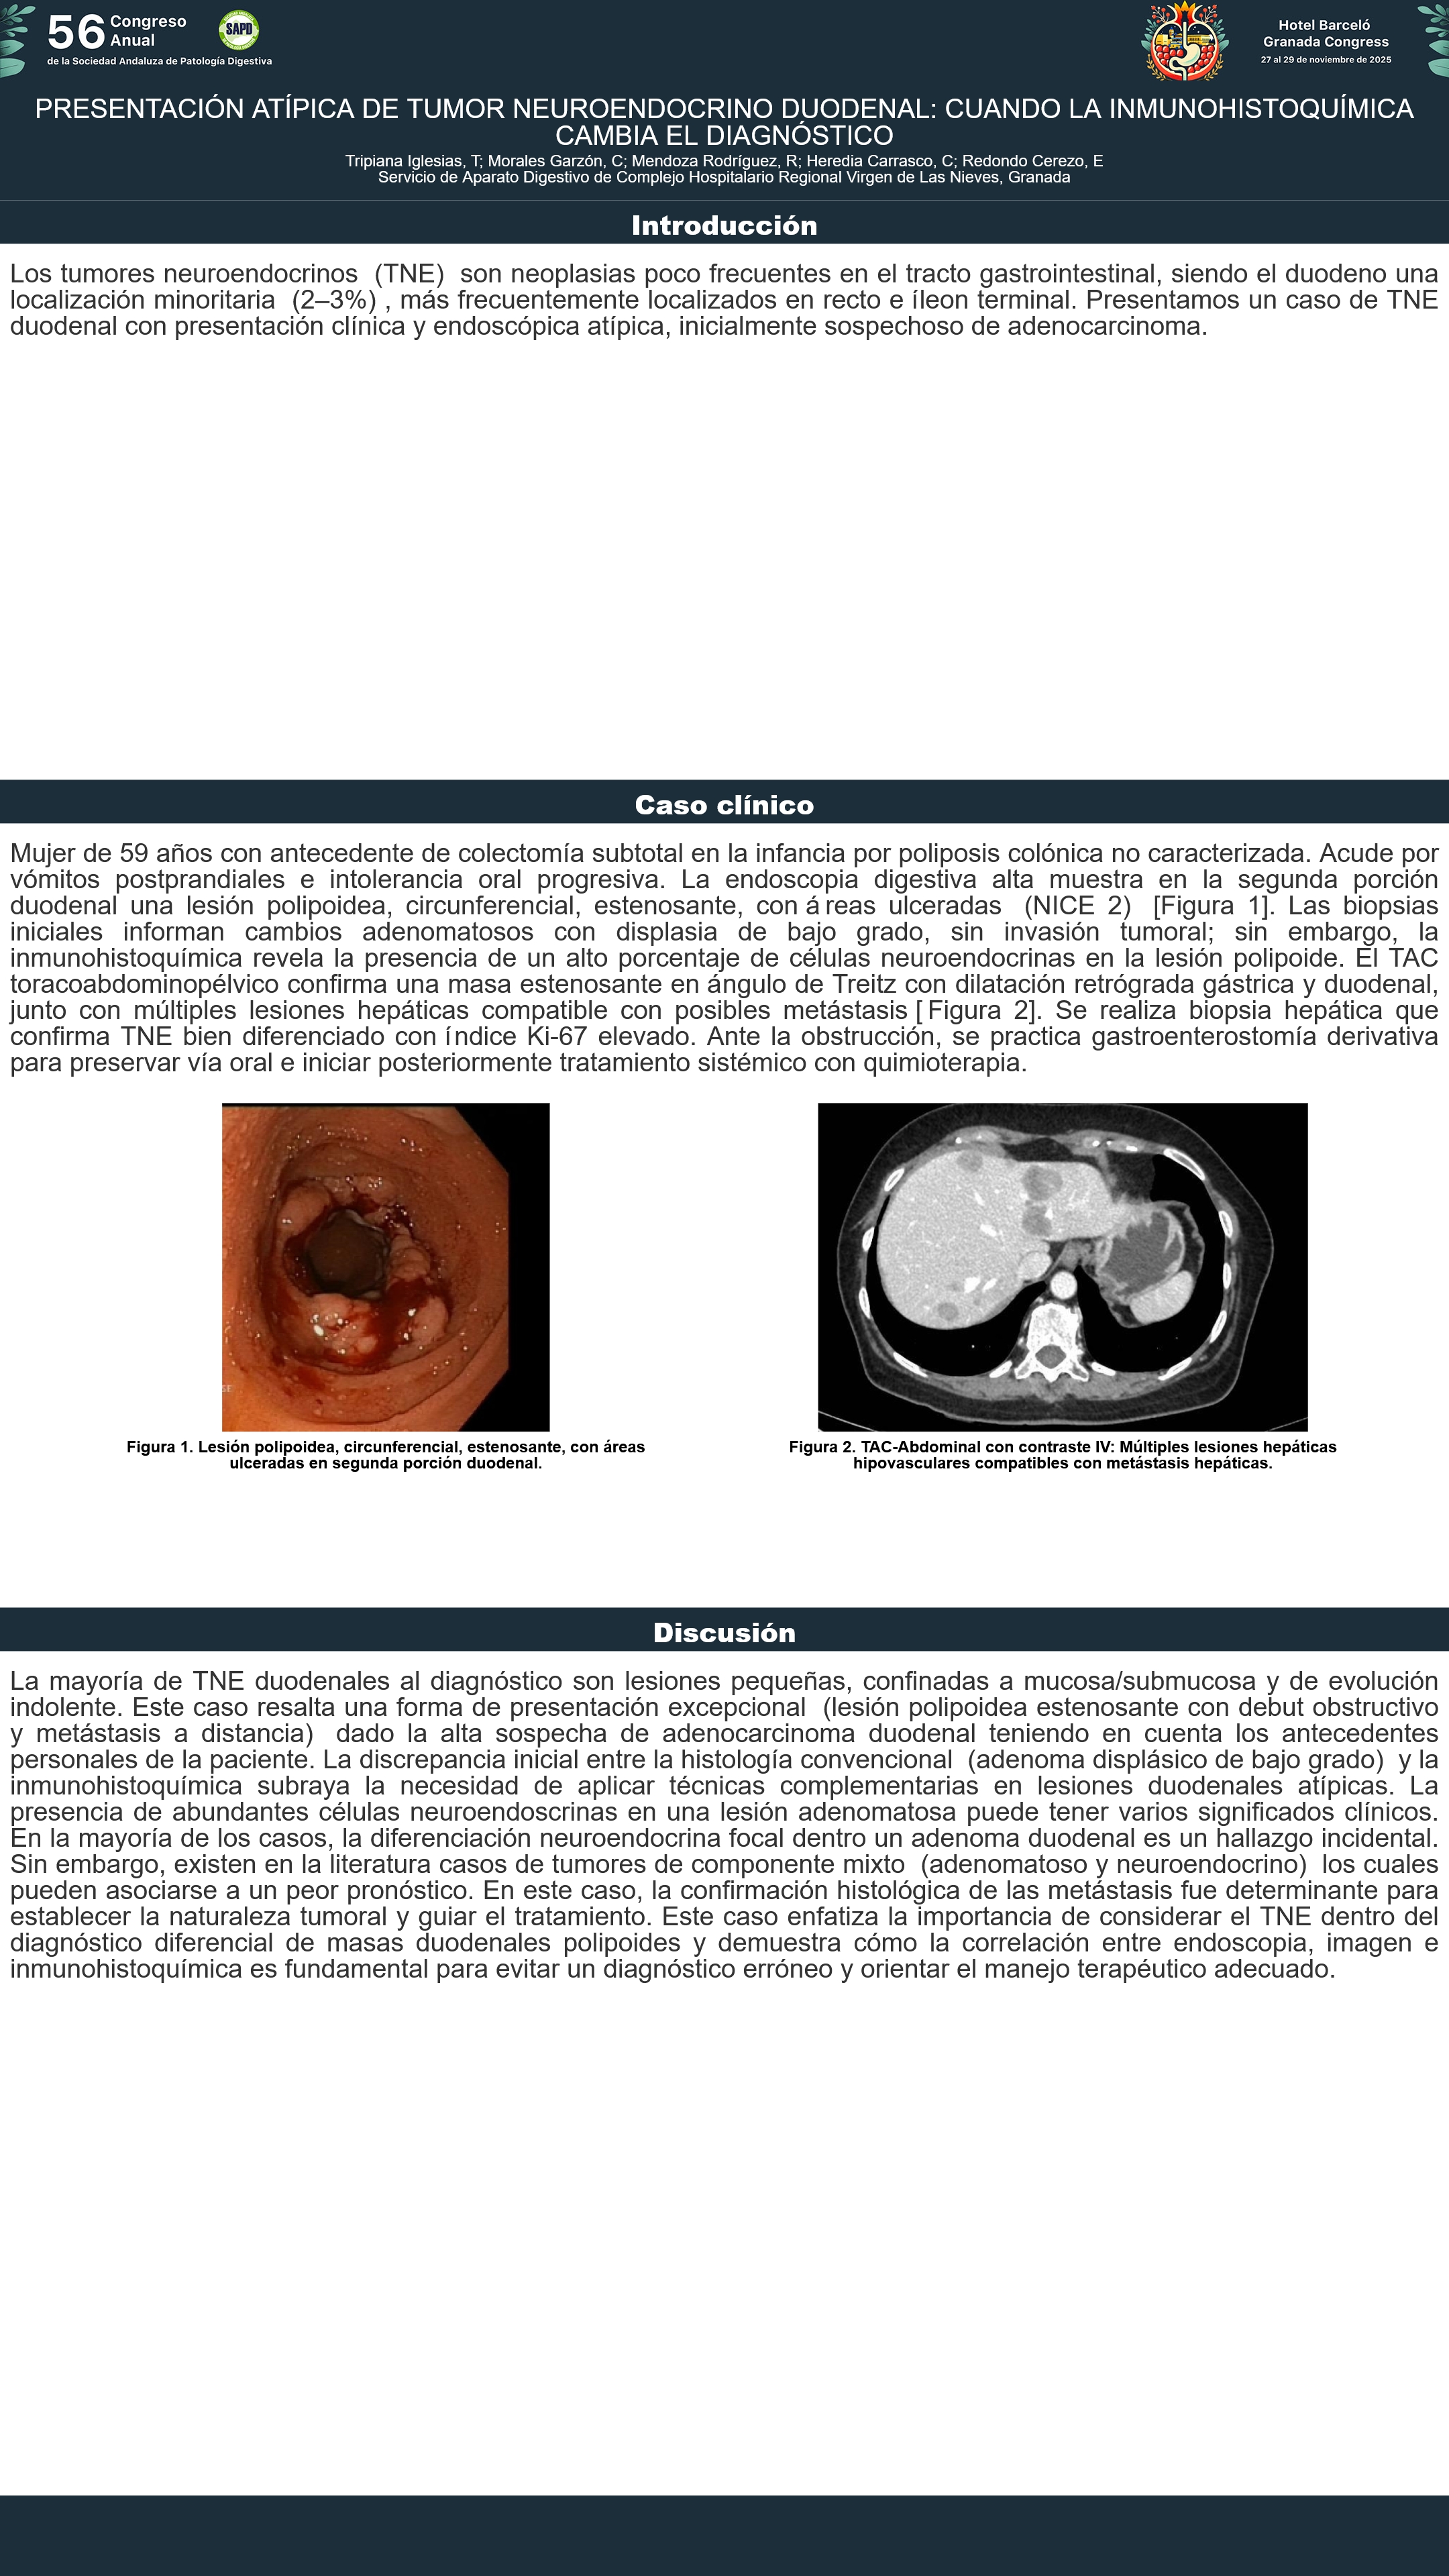

[CP-175] PRESENTACIÓN ATÍPICA DE TUMOR NEUROENDOCRINO DUODENAL: CUANDO LA INMUNOHISTOQUÍMICA CAMBIA EL DIAGNÓSTICO